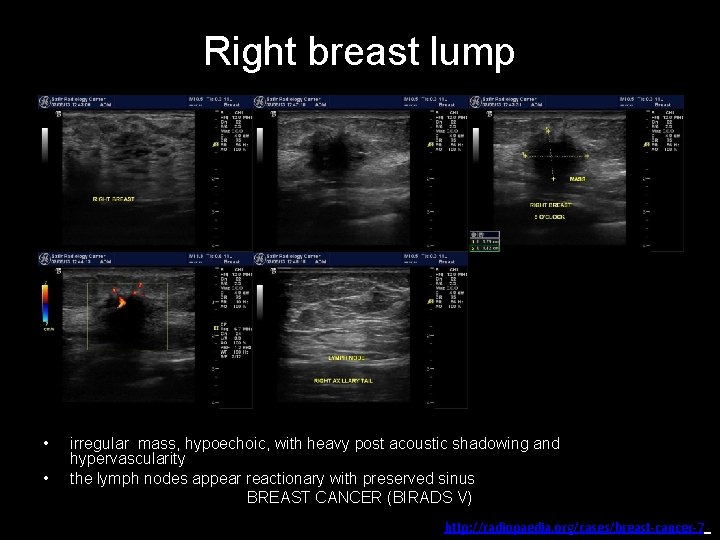

Right breast lump Right breast

Right breast lump • • irregular mass, hypoechoic, with heavy post acoustic shadowing and hypervascularity the lymph nodes appear reactionary with preserved sinus BREAST CANCER (BIRADS V) http: //radiopaedia. org/cases/breast-cancer-7